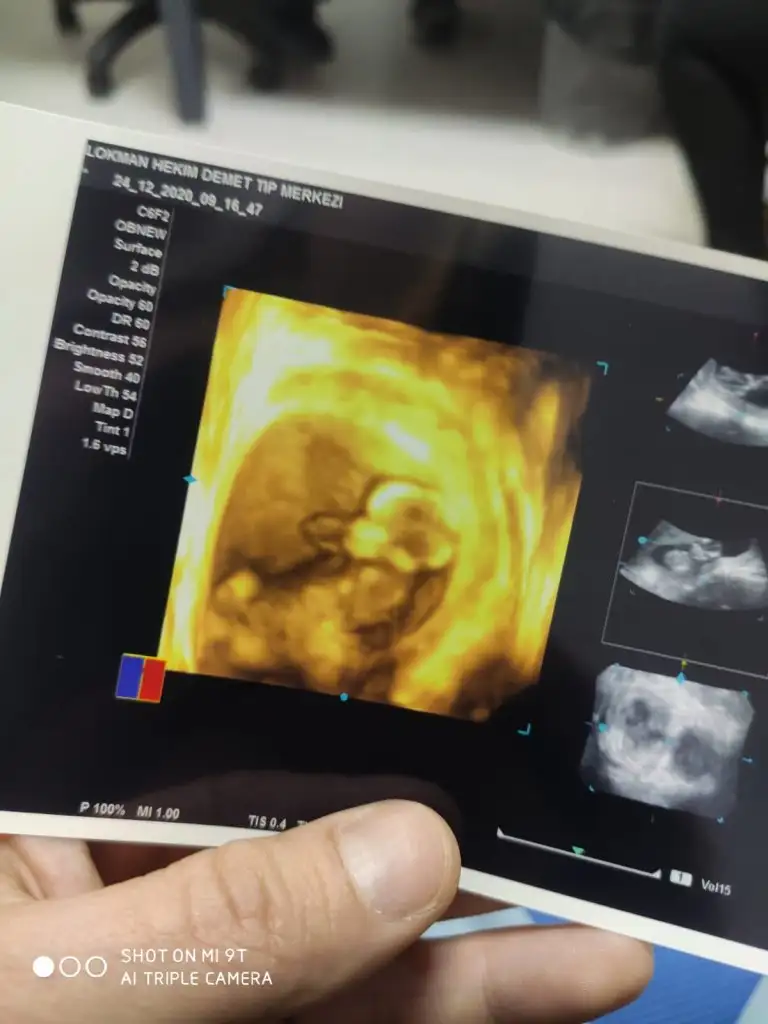

Merhaba buda 13 haftalık acaba şimdi netleşir miKarından ise erkek vajinalsa kiz tabiki en iyi 11 12 13 haftalar

Erkek görünüyorMerhaba buda 13 haftalık acaba şimdi netleşir mi

Emin olamadım başka USG varsa paylaşın sanki erkek gibi gibi ama emin değilim